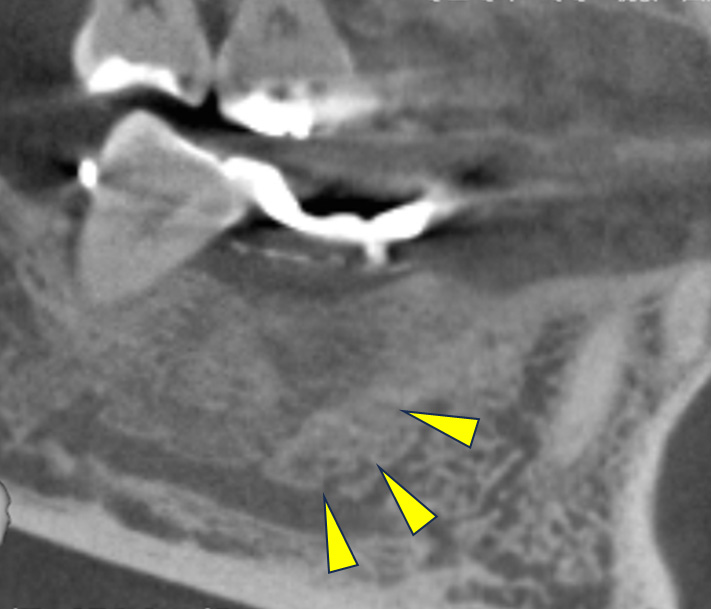

骨移植(人工骨+メッシュプレート)を行い、骨を造りました。

CT画像 -

インプラント手術を行いました。